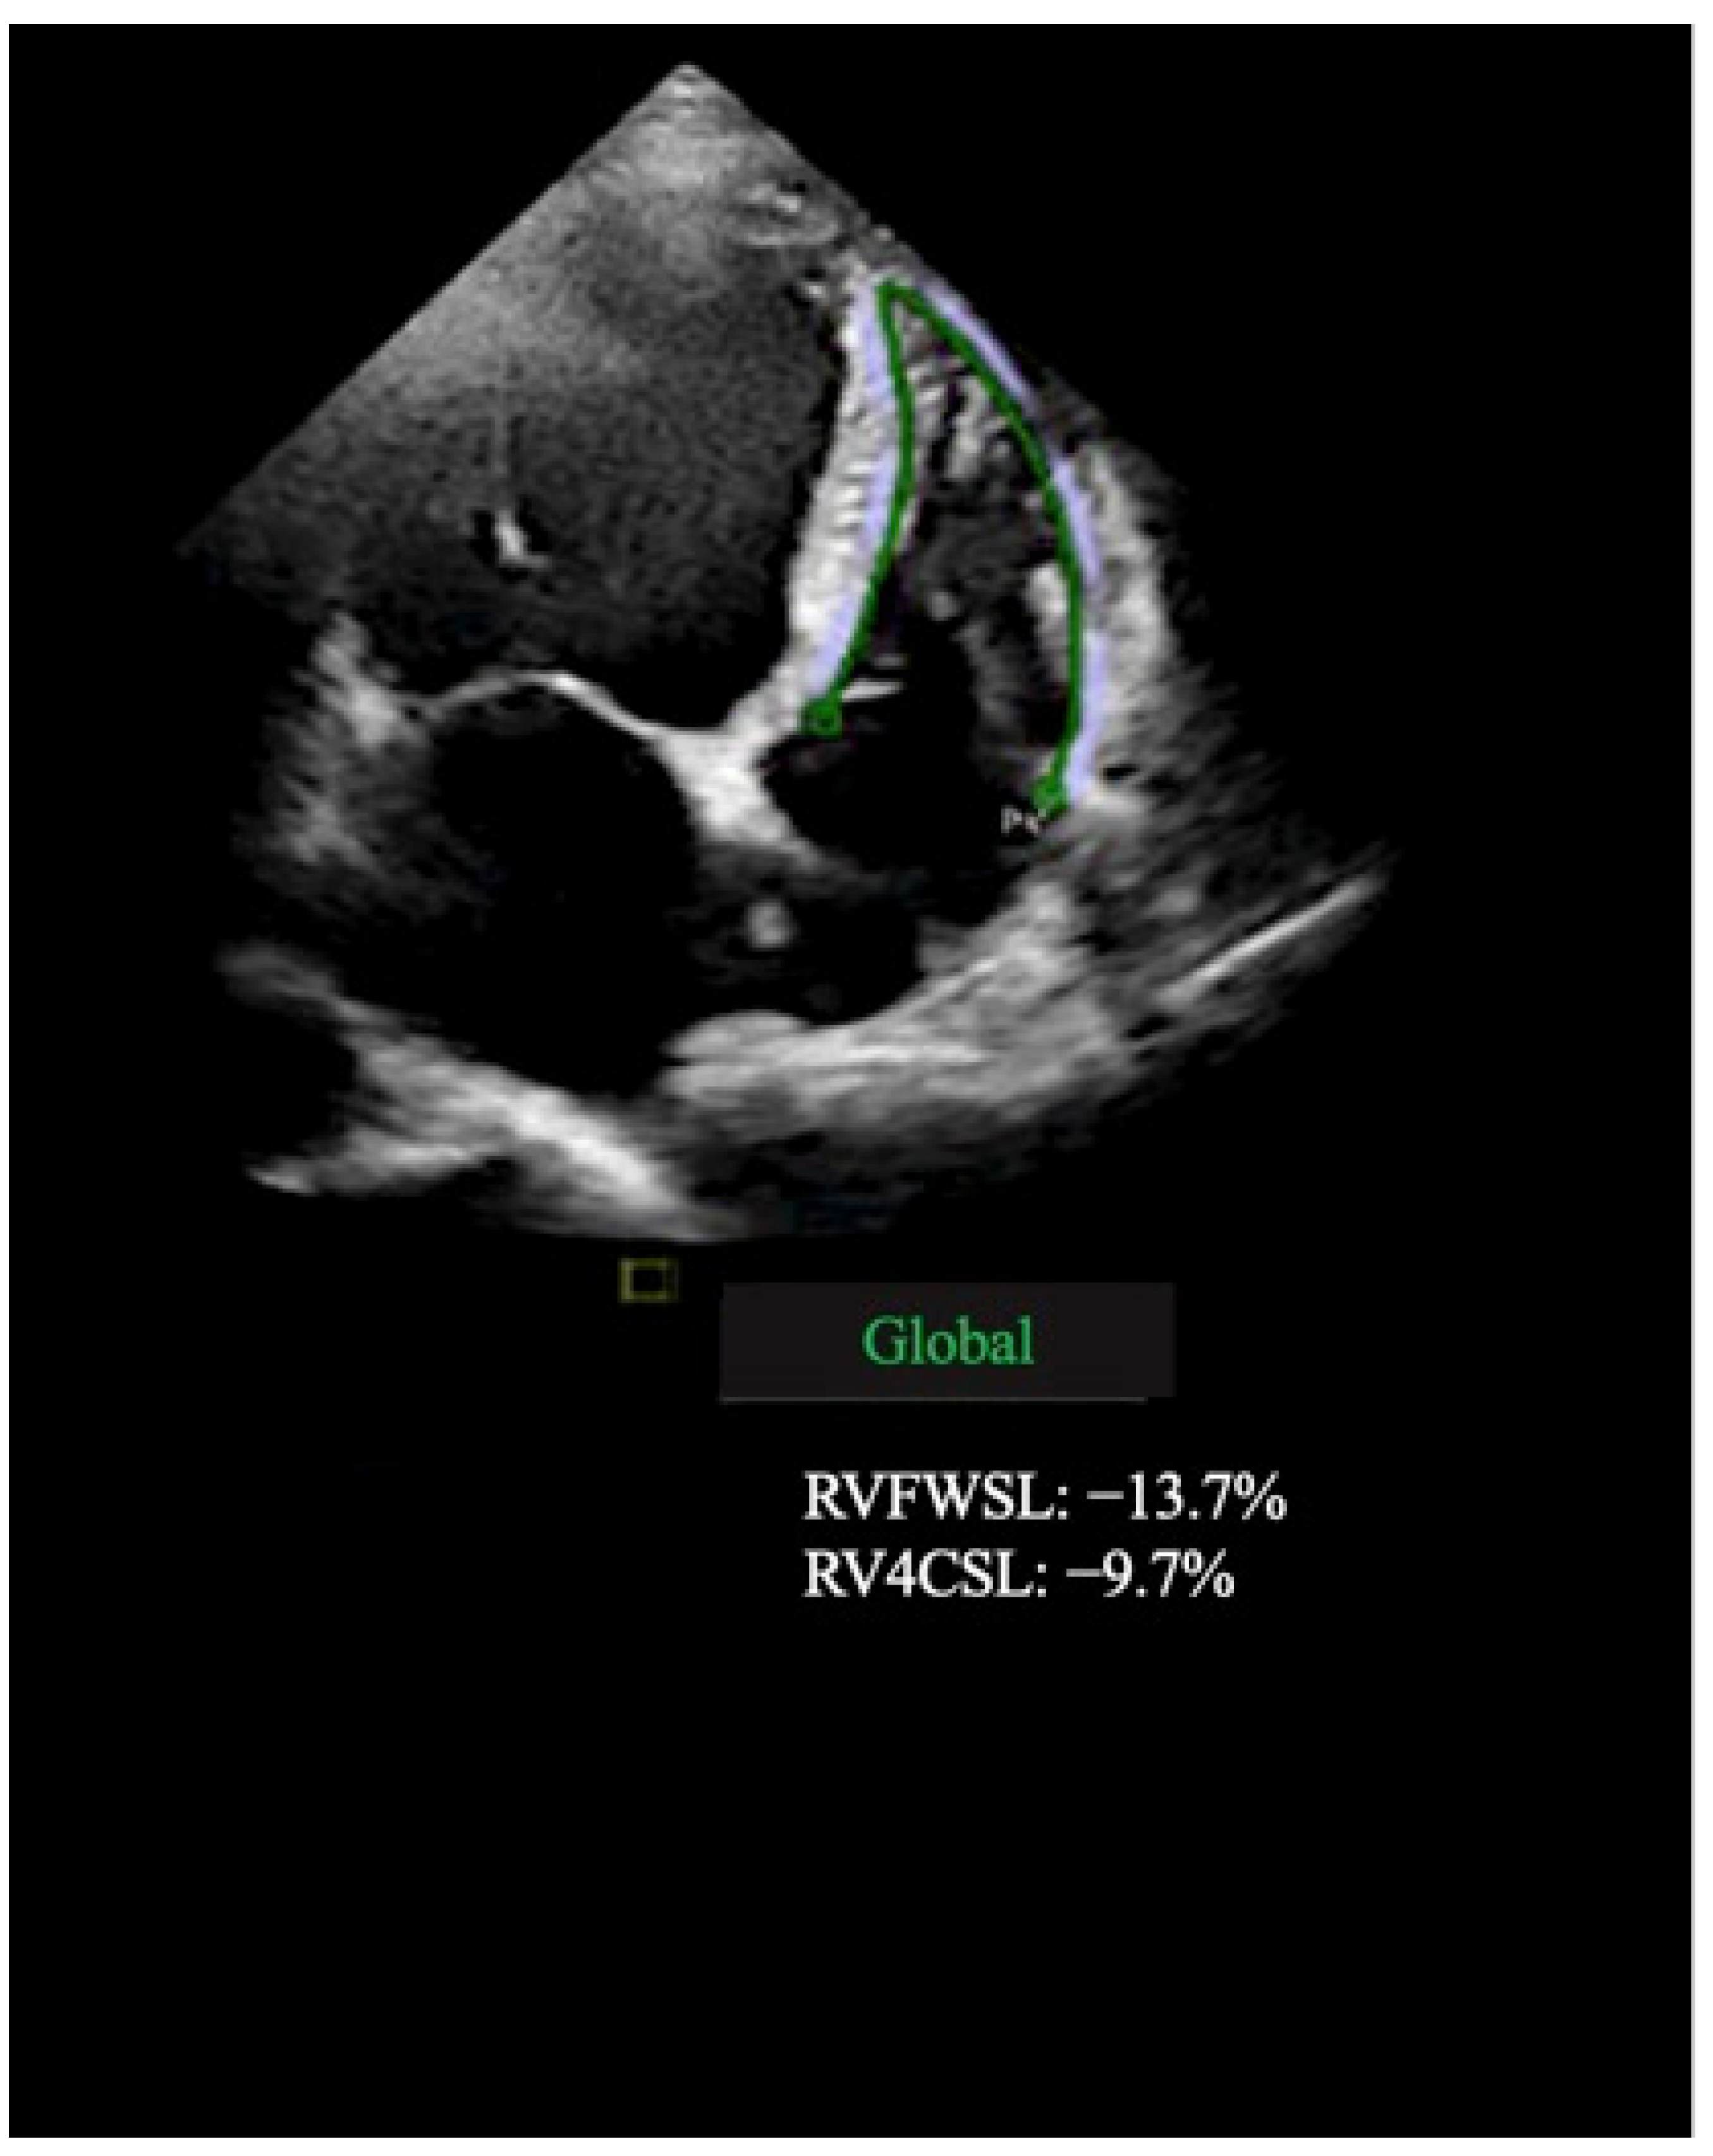

| RV free wall LS, % | −17.3 ± 2.9 | −19.0 ± 2.9 | 0.008 |

| RV GLS, % | −9.5 ± 3.5 | −13.2 ± 4.2 | 0.007 |

| RV FAC, % | 30.1 ± 5.9 | 33.5 ± 5.1 | 0.002 |